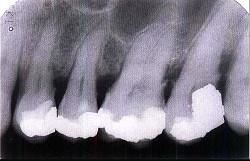

牙槽骨水平型吸收的特点是 ( )

- A.常形成骨上袋

- B.是最常见的吸收方式

- C.牙槽间隔、唇颊侧或舌侧的嵴顶边缘呈水平吸收

- D.牙槽嵴高度有明显降低

- E.以上均是

E